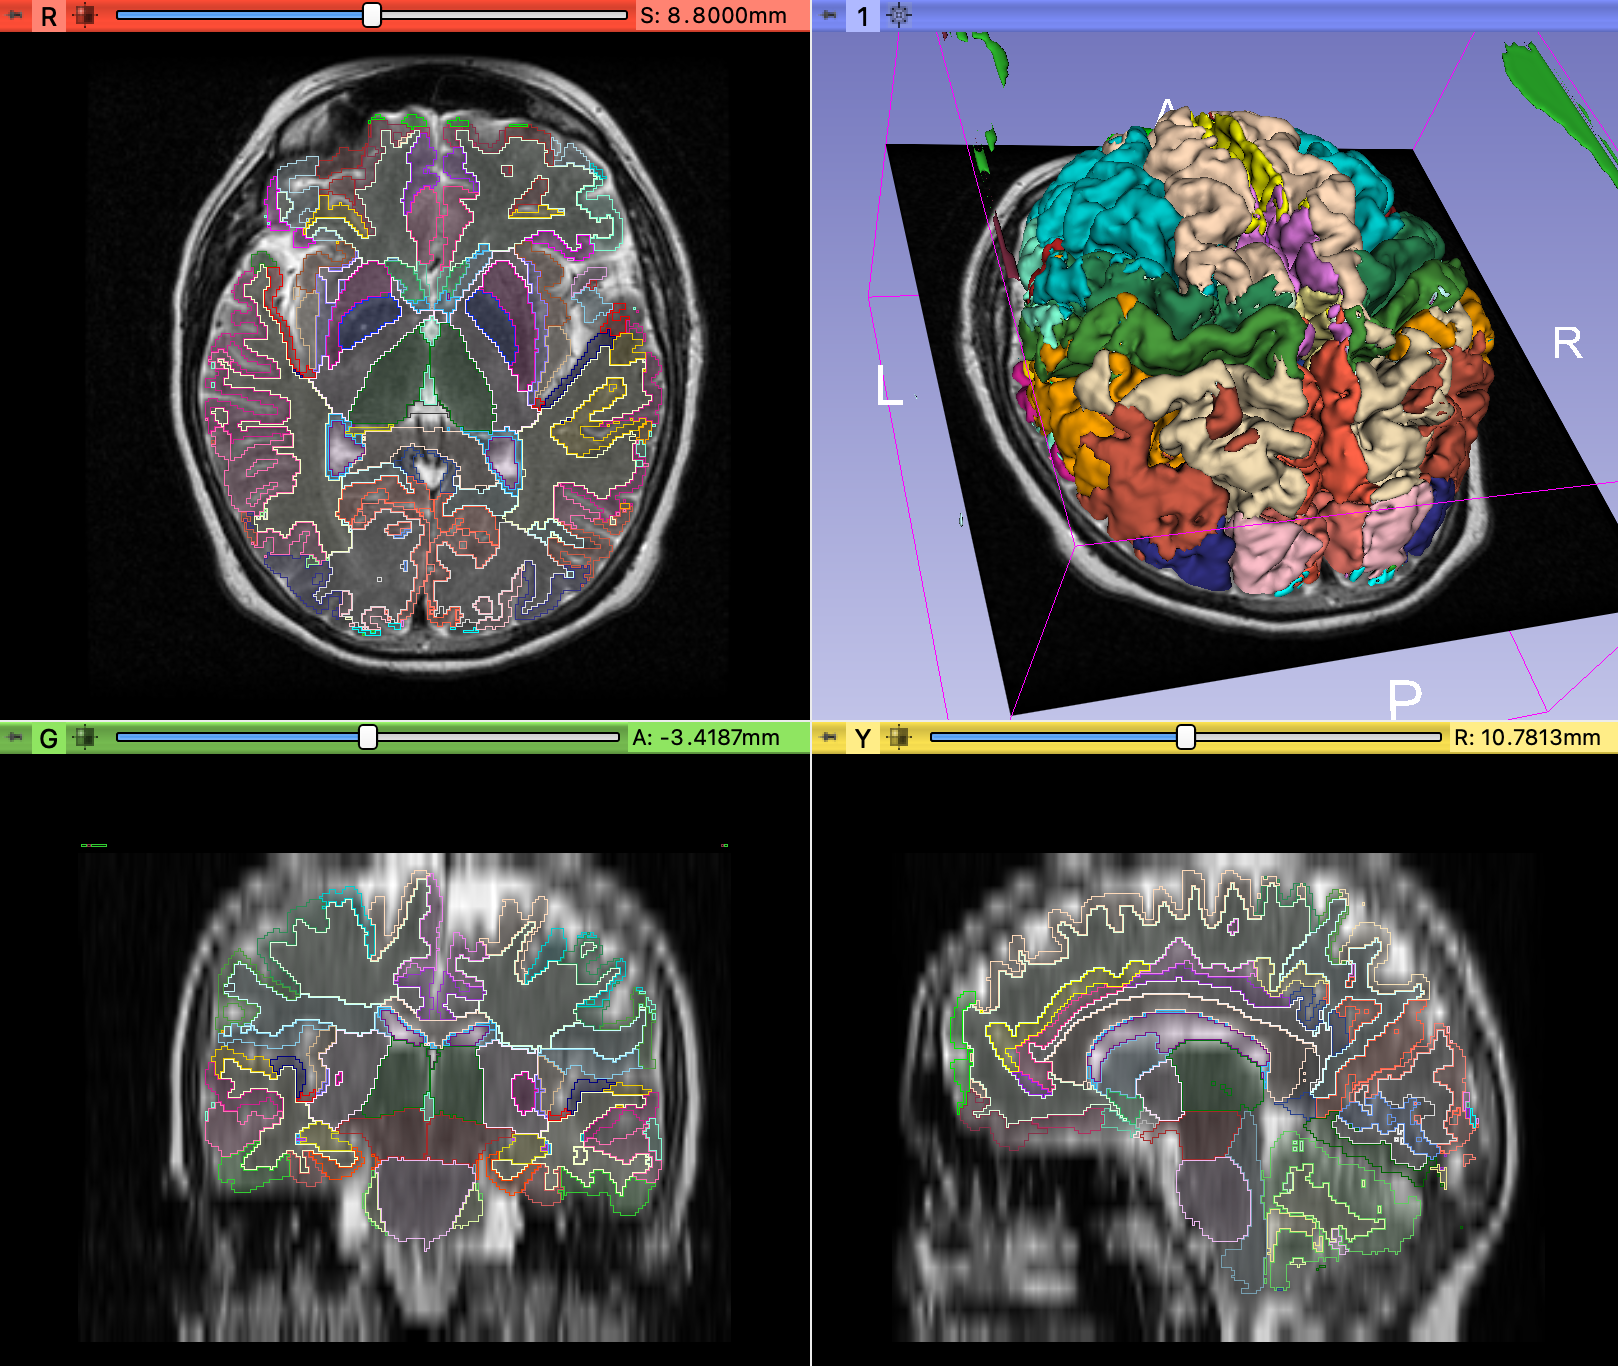

Brain Parcellation

Based on Li et al., 2017, On the Compactness, Efficiency, and Representation of 3D Convolutional Networks: Brain Parcellation as a Pretext Task. More info at the highresnet repository.

Parcellation run by @pieper on a synthetic 1 mm isotropic T1 MPRAGE generated from a 6.5 mm anisotropic T2 (using model from Iglesias et al. 2021):